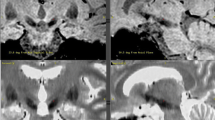

MER-STN started and ended more dorsally than respective dorsal and ventral MRI-STN borders on both sequences. Distances between dorsal MER-STN and MRI-STN borders were 1.9 ± 1.4 mm (T2) and 2.5 ± 1.8 mm (SWI). Distances between ventral borders were 1.9 ± 1.6 mm (T2) and 2.1 ± 1.8 mm (SWI). Dorsal borders were identified at a mean (± SD) distance of 2.9 ± 1.9 mm above target depth for T2; 2.7 ± 1.9 mm for SWI and 3.9 ± 1.9 mm for MER. Ventral borders were identified at a mean (SD) distance of 2.1 ± 1.8 mm below target for T2; 2.1 ± 1.8 mm for SWI and 1.0 ± 1.88 mm for MER. Mean STN length was 4.7 ± 2.1 mm on T2, 4.5 ± 2.2 mm on SWI and 4.9 ± 1.7 mm utilizing MER. Figs. 2 and 3 illustrate track representation on T2, SWI and following MER.

STN representation on T2, SWI, and MER along ME trajectory. This figure illustrates the representation of the MRI-STN and MER-STN along the MER track respective to each other and in relation to target depth. For reference, a microelectrode is schematically drawn next to the T2-STN, SWI-STN, and MER-STN representation along the MER track. This figure illustrates how the MER-STN starts more dorsally than the dorsal MRI-STN border and ends more dorsally than the ventral MRI-STN borders on both sequences

STN border representation on T2, SWI, and MER. This chart illustrates the representation of the MRI-STN and MER-STN along the MER track in relation to target depth. Bars illustrate the representation of the STN and its dorsal and ventral borders. The standard deviations for the mean borders are illustrated by the error lines. The y-axis represents millimeters from target depth (depth ‘0’), with positive values representing the dorsal aspect of the STN along the MER track and negative values the ventral aspect. MER-STN starts more dorsally than the dorsal MRI-STN border and ends more dorsally than the ventral MRI-STN borders on both sequences. T2-STN starts 2.9 ± 1.9 mm above target depth, SWI 1.7 ± 1.9 mm and MER 3.9 ± 1.9 mm. T2-STN lower borders were found 2.1 ± 1.8 below target depth, SWI 2.1 ± 1.8 mm and MER 1.0 ± 1.9 mm